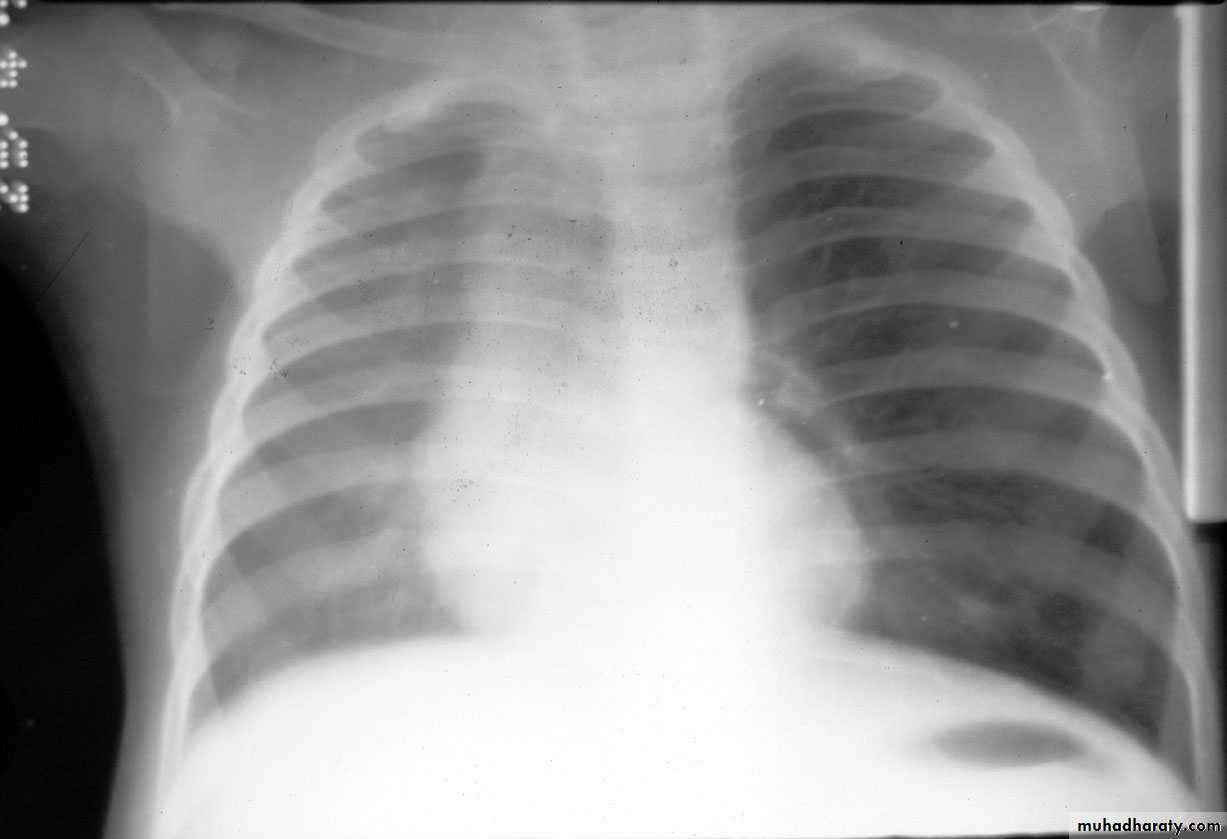

Pleural effusion ( free)